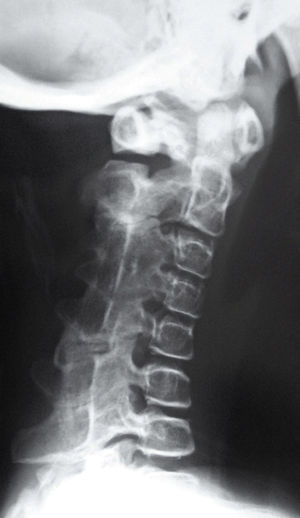

Los recién nacidos con FOP tienen un aspecto normal excepto por la presencia (en la práctica totalidad de ellos) de malformaciones en el dedo gordo del pie, siendo el hallux valgus congénito el sello más característico de la enfermedad (fig. 1)13,14. Aunque se suelen reconocer más tarde (e incluso pasan inadvertidas o son erróneamente interpretadas), el componente displásico de la FOP se puede manifestar por diversas anomalías esqueléticas congénitas que aparecen con una frecuencia variable pero casi siempre elevada. Entre estas malformaciones destacan: otras anomalías en los dedos de las manos y los pies distintas de las del dedo gordo del pie (acortamiento de falanges, metatarsianos y metacarpianos, sinostosis, clinodactilia)15; aumento de tamaño y fusión de la facetas posteriores con hipoplasia del cuerpo vertebral en la columna cervical (fig. 2), que puede acabar formando un bloque16–18; osteocondromas, sobre todo evidentes en la región medial de la tibia19, y cuello femoral corto y ancho20.